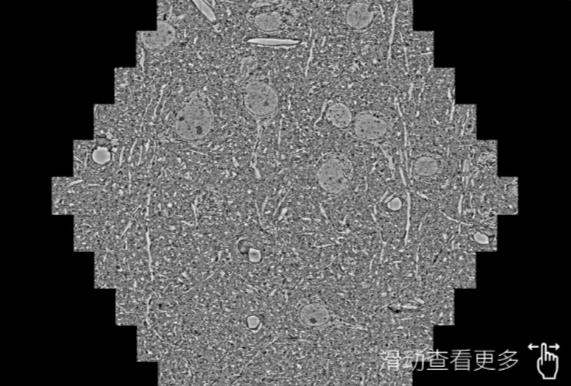

鼠脑切片。左图使用洛阳蔡司洛阳扫描电镜MultiSEM706对165μmx143pm面积区域成像,耗时仅需1.5秒。右图为鼠脑切片中30μm区域放大效果。样品由芝加哥大学B.Kasthuri提供。